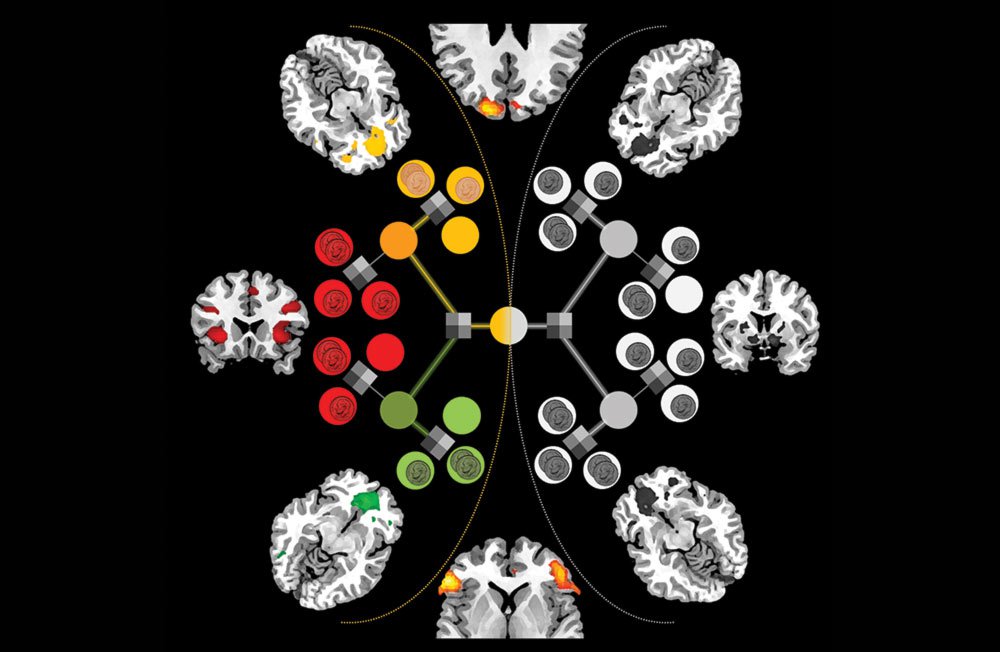

We study brain activity by putting your head in an fMRI scanner. "MRI" stands for magnetic resonance imaging, and you've probably had one if you've had a sports injury. The "f" stands for "functional," and an fMRI scan detects changes in the oxygenation levels in the blood. If a certain part of the brain is active, its oxygen supply increases. We map those increases onto the brain's anatomy in 3-D while our volunteers perform some task that involves learning.

We're also interested in how the brain changes its expectations. As you play the machines, you're constantly revising your estimate of which machine is better. We have computational models that we think represent how the brain internalizes feedback, and we're trying to find brain areas where the activity matches those models.